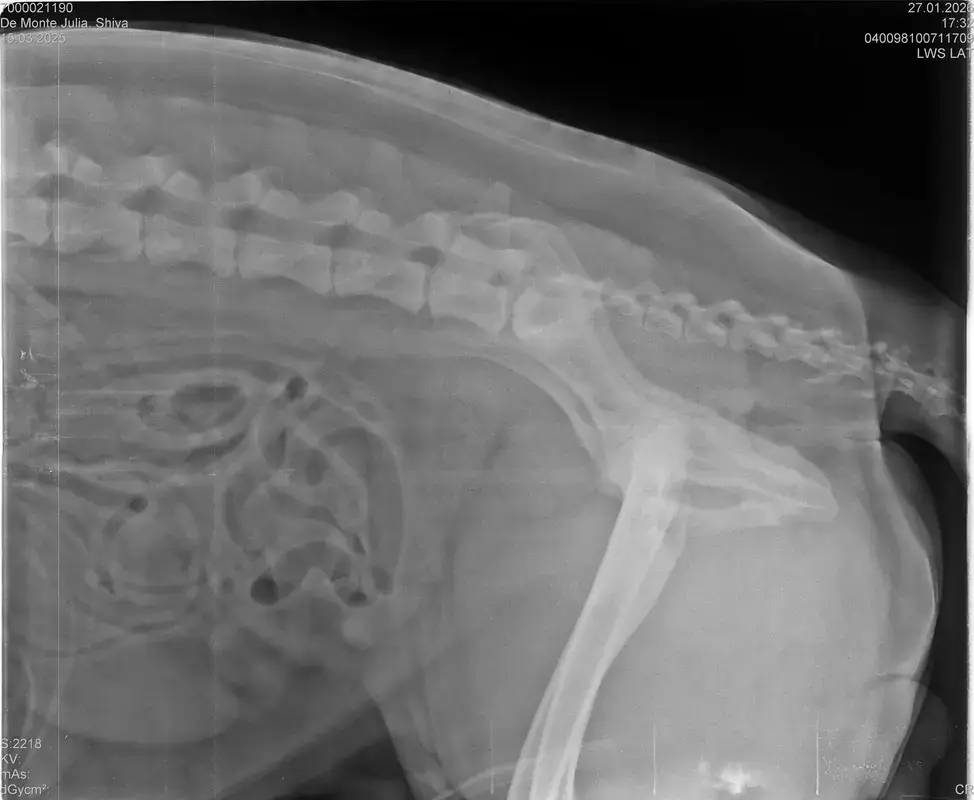

Vorige Woche kam mir Shiva verändert vor, nicht der aufgeweckte Spaßvogel der er sonst ist. Ich dacht vl ist er im Garten iwie blöd ausgerutscht weil unser gesamtes Grundstück über Wochen von einer dicken Eisschicht überzogen war. Er lag viel rum, zuviel da er doch zu den Wirbelwinden unter den Junghunden gehört. Er quetschte sich zum schlafen an mich ran, was auch untypisch für ihn ist. Er ist immer so „iiiii fass mich nicht an“. Ich nehms ihn nicht böse er ist nicht der große Kuschler :D Hat er wohl von mir :D :D aber er pickte nur an mir dran, ruhen ohne Körperkontakt war nicht möglich. Fand ich schön aber da ich wusste dass es nicht Shiva ist machte ich mir schon Sorgen… Am nächsten Tag wollte ich ihn bürsten alles war wie immer, er legte sich hin und sah mir zu wie ich einen Fellberg stapelte. Bei seinen Hinterpfoten hörte ich auf und dachte mir ich fühl mal vorsichtig.. Plötzlich knurrte er mich an vor Schreck weil ich damit überhaupt nicht gerechnet hatte zuckte ich reflexartig zurück (was lt Trainerin ein Fehler war)… Aber ich hab nicht mit einer derartigen Reaktion gerechnet, Shiva hatte schon 2 kleine Verletzungen die ich ohne Probleme verarzten konnte. Am nächsten Tag gings ab zum TA. Mit Maulkorb da ich nichts riskieren wollte. Nach der Untersuchung wo er auch mehrmals knurrte gings ab zum röntgen. Und das riss mir den Boden unter den Füßen weg. Dann die Aussage von der TA „ich weiß sie wollen einen gesunden jungen Hund aber das ist Shiva leider nicht“. Was jetzt? Er ist so ein aufgewecktes Kerlchen, absolute Lieblingsbeschäftigung ist Parcour. Er macht es so gern, ja auch UO und Suchspiele aber das leuchten in seinen Augen wenn wir Geräte machen :( (er macht noch keine schweren Geräte wie A Tafeln oder springen… Aber die seichten macht er mit absoluter Leidenschaft.. Ruhe halten über mehrere Monate… nur langsames gehen oder schnüffeln.. puh ich weiß nicht wie ich ihm verbieten soll zu rennen und zu toben… Vl habt ihr Tipps für mich. Im Anhang der Befund und ein paar Bilder vom kleinen Wirbelwind. <3

• Naja die Diagnose kommt von einem „Facharzt“, lt TA war ihrerseits alles i.O. Sie wollte noch sicher gehen und die Bilder zur weiteren Befundung einschicken und das kam dabei raus. Und der Therapievorschlag beläuft sich auf Ruhe, Ruhe und noch mehr Ruhe. Und einer Schmertherapie von Gabapentin 800mg 1/2 Tablette 2x tgl, Carprodyl 120mg 1 1/2 Tabletten 1x tgl und TamaCan CBD Tropfen 10-15 Tropfen 2x tgl. 1x in der Woche soll ich telefonisch Auskunft geben wie es Shiva geht. Das ganze mal für 14 Tage. Sie meinte noch sie hat viele Junghunde die ein Leben lang Schmerzmittel nehmem müssten. Die Röhrenknochenentzündung heilt in der Regel von selber der Rest gehört beobachtet… Ich weiß im Moment auch nocht so recht.. Er tut mir nur wahnsinnig leid mit sovielen Diagnosen und für mich war erstmal vorrangig ihn schmerzfrei zu bekommen. Das ist er inzwischen und versteht die Welt nicht mehr warum er nicht wie sonst spielen und arbeiten darf. Im Anhang noch Röntgenbilder falls sich jemand damit auskennt bzw Interesse hat..

• Ok, die Röntgenbilder sind aber auch extrem schlecht.

Panostitis ist idR sehr schmerzhaft, aber nicht unüblich und heilt in der Regel von alleine aus, wichtig dabei ist schonen und Entzündungshemmer zu geben, damit das nicht chronisch wird. Ich denke, dass die Akut bemerkbaren Schmerzen hauptsächlich davon kommen. Also da passt die Empfehlung deiner TÄ für's Erste auf jeden Fall.

Wenn dieser Panostitis-schub rum ist, würde ich dem Rest nochmal nachgehen. Man kann bei Dr. Tellhelm ( SV Gutachter) ein privatgutachten in Auftrag geben, das kostet um die 100€. Da kriegst du halt ne konkrete Einstufung und nicht "verdacht auf" und "könnte hiermit ODER damit in Verbindung stehen", etc.

Ich denke aber, dass du für ein Gutachten von Tellhelm nochmal neu röntgen lassen musst, ich finde, dass das Bild der Hüfte (HD und LÜW wird da beurteilt) und die Draufsicht auf die Ellenbogen (nötig zur Beurteilung von ED) unterirdisch sind!